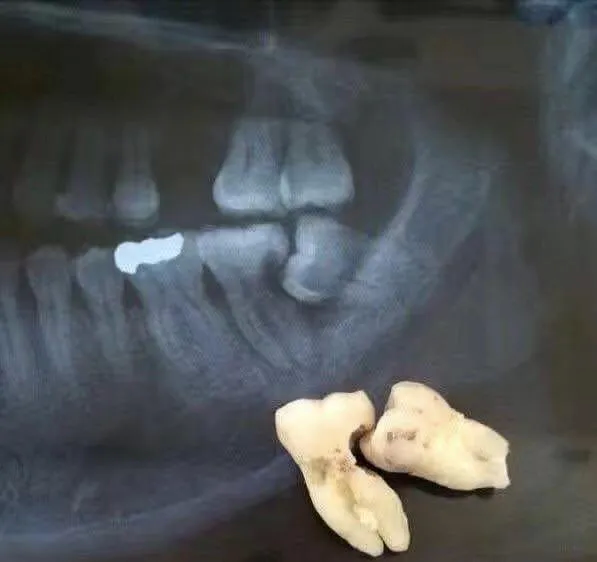

智齿龋坏:当智齿出现严重龋坏,且治疗价值不大时,建议拔除,这包括邻接面龋坏难以处理或需要根管治疗的情况。

影响其他牙齿:智齿的生长可能对邻牙造成挤压,导致邻牙损坏或移位。在这种情况下,为了保护其他牙齿的健康,需要拔除智齿。

严重食物嵌塞:智齿位置不良,容易与前牙食物嵌塞,建议拔除。